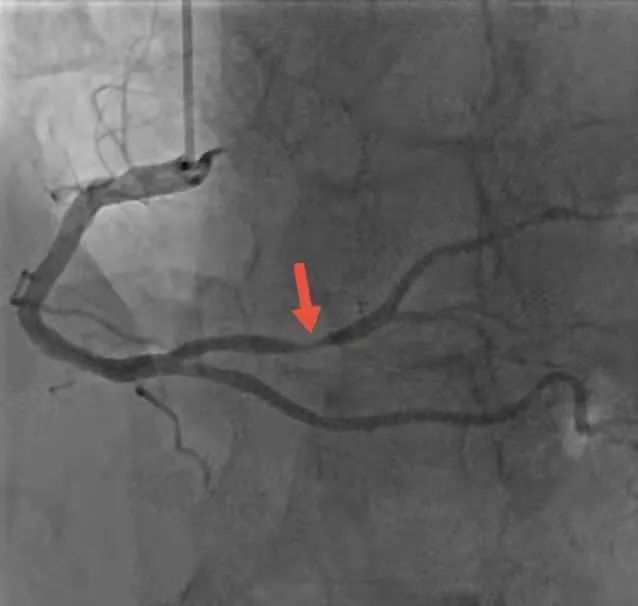

病变血管(右冠脉左室后支)

在医院心内科和导管室医护人员全力配合下,短短半小时医生便完成手术,为肖恩顺利植入心脏支架,成功开通病变血管。